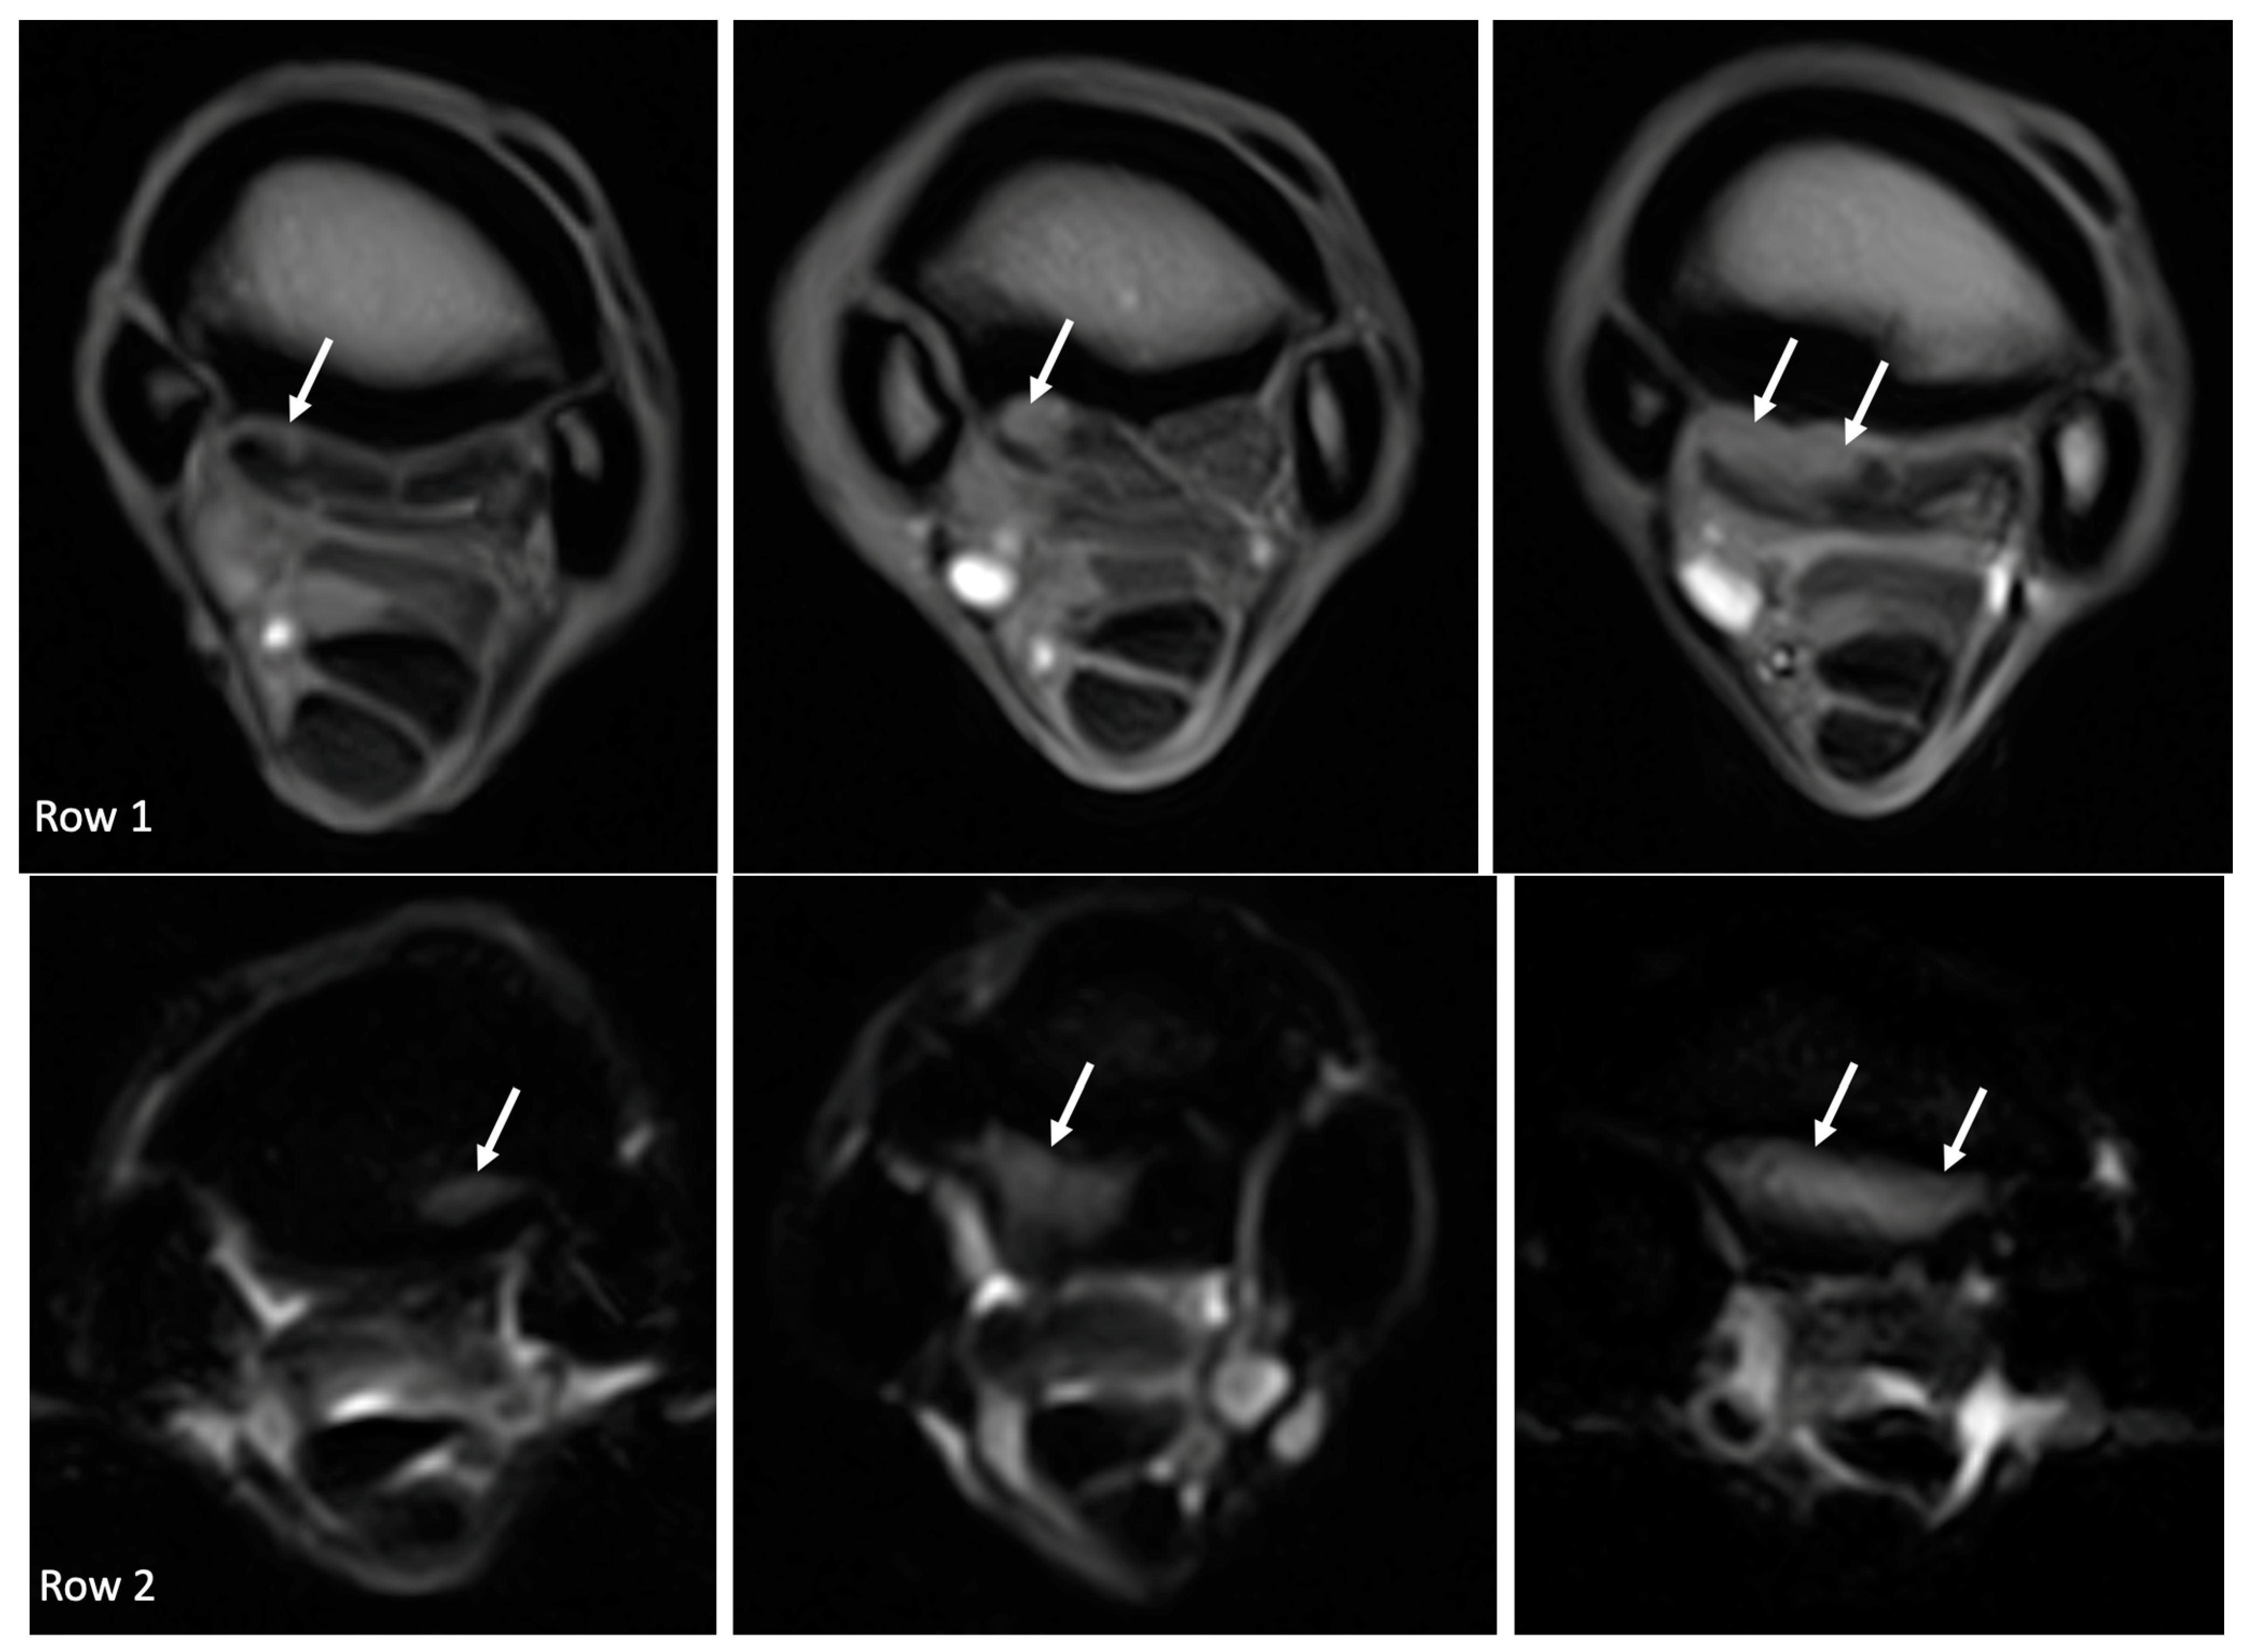

| McIII hyperintense STIR signal | 16/18 (89%) | 16/16 (100%) | - | - | - |

| McIII hyperintense STIR signal | Grade 0: 2 limbs Grade 1: 5 limbs Grade 2: 3 limbs Grade 3: 8 limbs | Grade 0: 18 limbs Grade 1: 0 limbs Grade 2: 0 limbs Grade 3: 0 limbs |